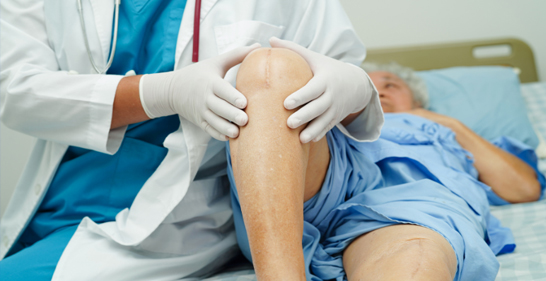

Recovery & Rehabilitation

Icon First Few Days: Pain management, early mobilization - usually on day one post surgery, Climbing stairs up and down before discharge from the hospital, and physiotherapy .

Icon 2-6 Weeks: Increased mobility

Icon 3 Months & Beyond: Strengthening exercises and return to daily activities.